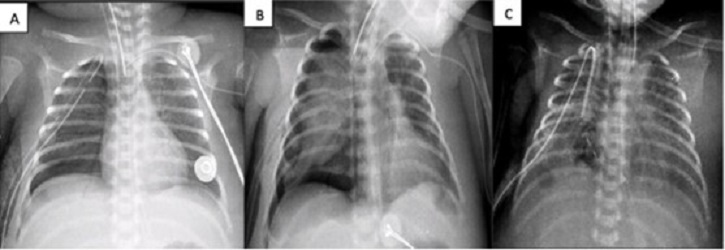

Figure 3

A) Chest x-ray post 1st ABPP. B) Chest x-ray post 2nd ABPP. C) Chest x-ray post fibrin patch.

A 17-day-old male, born at 29 GW (1200 g), was diagnosed with NEC, respiratory distress syndrome, and pulmonary hypertension. (NEC required ex-laparotomy with Santully type ileostomy). Placed on CMV with FiO2 at 81% due to right tension pneumothorax. Air leakage persisted for 4 days along with increasing ventilatory parameters, that warranted ABPP (though the PAL criterion was not met fully). On day 23, ABPP was re-performed. No clinical improvement was seen. The patient developed hemodynamic instability requiring emergent thoracotomy. Multiple lesions were seen in the inferior lobe of the right lung. Primary closure was done without success, therefore fibrin patch (bovine serum purified albumin glutaraldehyde) was placed. Improvement was evident at 24 hours. The chest tube was removed on the 33rd day of life (Fig. 3).